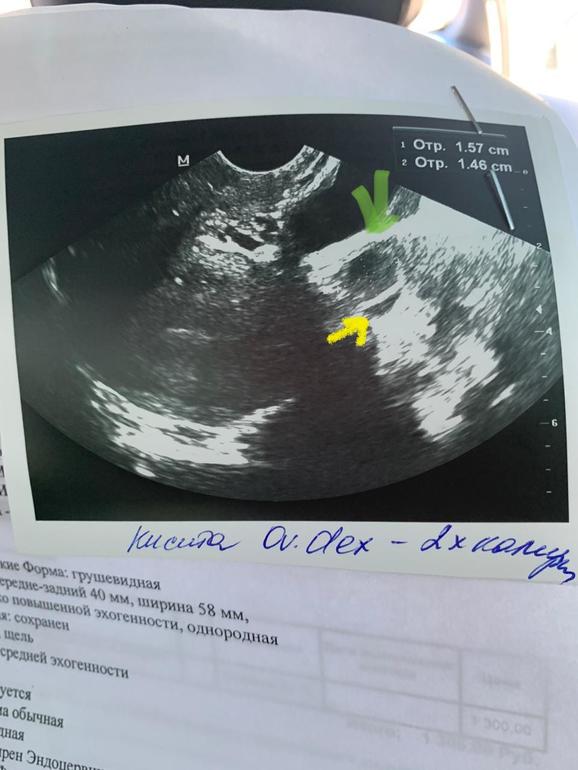

Узисты могут путать , с этим полностью соглашусь !!! Мне на 8 дц узист сказала что у меня киста В ПЯ... причём двухкамерная 14мм (что по минимальным нормам размера кисты меньше в два раза.. ( но из не было никогда и проблем с циклом тоже ) она сказала что все плохо и воспалено и о не ждать ... Что мне показалось очень странным и на 10дц я пошла к другому врачу и О ЧУДО! Киста двухкамерная превратилась в Дф и Камера вторая испарилась 🤦🏼♀️И ничего у меня не воспалено , в е в норме , просто она сказала о будет чуть раньше , лови тестами , ну и на след день ЯБ и через день яркий положительный тест на О 🙏🏻Сравнив снимки с первого и второго узи даже мне понятно , что первый узист долбаный слепыш ! Помимо моего дф замерила ещё что-то как одно целое и поставила диагноз двухкамерная киста ! Но даже на снимке видно что это не так ! Сейчас прикреплю вам , посмотрите ! А я то испугалась !залечила бы не понятно что ....

вот это типо двухкамерная киста ....